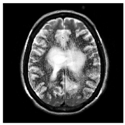

This work collects images from the Kaggle Brain MRI for Brain Tumor Detection dataset, which consists of 253 files with cancer and non-cancer brain images. The sample MRI is illustrated in Figure 2. The dataset has two folders: no tumor encoded as 0 and tumor as 1. The labeled data is more helpful in extracting the patterns from the MRI, which is used to predict the new images related output. The collected image consists of noise information that reduces the performance of brain tumor recognition accuracy. Therefore, image noise should be eliminated to improve the overall prediction efficiency.

Figure 2.

MRI samples Normal Brain MRI (Y1 to Y8) Benign tumor MRI (Y9 to Y15) Malignant tumor MRI (Y16 to Y21).